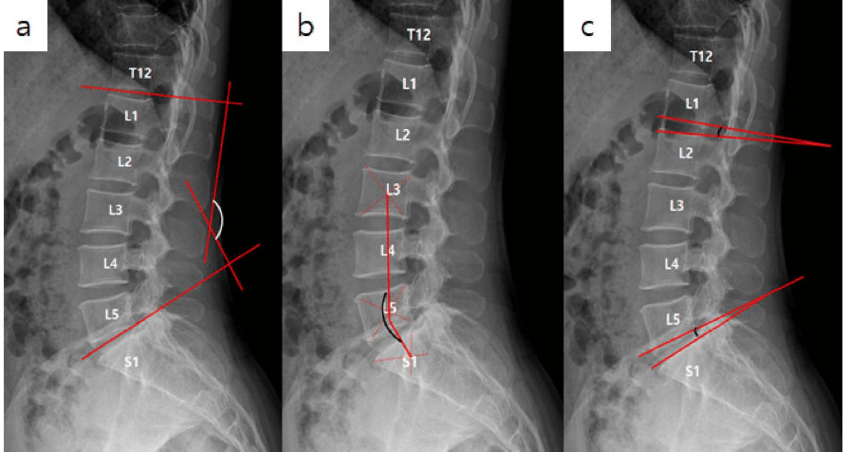

A thorough physical exam would include a complete medical history including any spinal surgery or genetic predispositions. Also, monitor patients’ postures and take digital photographs of them using software to analyze their postures. All necessary X-rays will be taken. These images give important information about the effect of abnormal curves on overall spinal mechanics.

The loss of one or more natural and healthy curvatures in the spine can cause a disruption to the whole spine. To simplify the term and answer the question: What is straightening the lumbar? The lumbar is the lower back. A straightening of its lordosis is when there is a loss in that section’s natural C-shaped curve.

The curvatures of the cervical and lumbar spines are lordotic. However, the thoracic curve has a kyphotic curvature, which is an outward curve that forms a reverse “C” shape. There are normal and natural curvature-degree levels. However, problems can arise if the curvature is too or too severe.